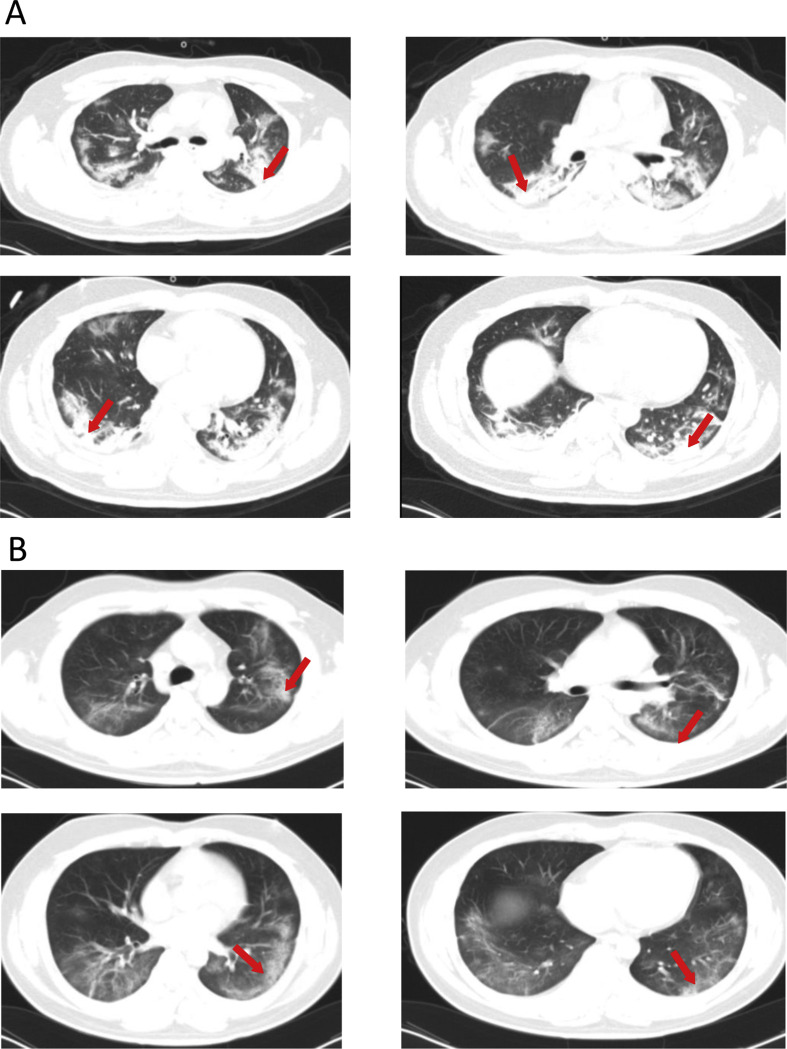

Admission examination showed a temperature of 36 °C, a pulse of 85/min, a respiratory rate of 35/min, a blood pressure of 117/84 mmHg. Physical examination showed no abnormalities. Laboratory studies showed increased white blood cell (WBC) count (17.64 × 109/L; normal references: 4–10 × 109), neutrophil count (15.45 × 109/L; normal references: 2.0–7.0 × 109), and lymphocyte count (0.6 × 109/L; normal references: 0.8–4.0 × 109). Blood chemistries revealed elevations in C-reactive protein (CRP) (348.56 mg/L; normal references: 0.00–8.20 mg/L), and erythrocyte sedimentation rate (ESR,140 mm/h; normal references: 0–15 mm/h), fasting plasma glucose (FPG, 7.13 mmol/L; normal references: 3.9–6.10 mmol/L), alanine aminotransferase (ALT, 70 U/L; normal references: 5–40 U/L), aspartate aminotransferase (AST, 63 U/L; normal references: 8–40 U/L), blood urea nitrogen (BUN, 11.21 mmol/L; normal references: 2.9–8.2 mmol/L), and procalcitonin (PCT, 0.162 ng/mL; normal references: <0.046 ng/mL). Chest computed tomography (CT) scan revealed diffuse multiple patchy exudates, which were more marked in both lower lungs, suggesting infectious lesions (Fig. 1 A). Echocardiography showed no apparent abnormalities. Blood gas analysis showed pH 7.287, PCO2 48.6 mmHg (normal references: 35–45 mmHg), PO2 69.8 mmHg (normal references: 80–100 mmHg), BE: −4.3 mmol/L (normal reference: −3.0 to 3.0 mmol/L), and HCO3 - 20.8 mmol/L. His influenza B test was negative, and the nucleic acid test of nasopharyngeal swabs was positive on two occasions. A diagnosis of severe COVID-19 pneumonia and moderate acute respiratory distress syndrome (ARDS) was made and the patient was placed under isolation.

Figure 1.

(A) Chest CT scan of a 32-year-old male with cough and breathing difficulty on February 6 reveals diffuse multiple patchy exudates, which are more marked in both lower lungs, suggesting infectious lesions. (B) Chest CT scan on February 20, 2020 shows diffuse bilateral ground glass opacities and partial exudation, which are markedly improved compared with admission CT scan findings.

The patient received assisted continuous positive airway pressure (CPAP) ventilation on February 4, 2020. Apart from supplemental oxygen (Fi: 0.4–0.6) for 5 days, he was treated with ceftazidime (2.0 g twice daily) for 13 days, and levofloxacin (0.5 g/day) for 3 days, recombinant interferon α aerosol (500 × 106 U, twice daily) for 17 days, lopinavir-ritonavir (0.2 g twice daily) for 5 days, and oral umifenovir (0.2 g, three times daily), intravenous esomeprazole (40 mg twice daily), injectable Xuebijing for 13 days, budesonide aerosol twice daily and methylprednisolone (40 mg/day q12h) for 5 days. Meanwhile, the patient received enteral nutritional support and psychological intervention was also provided to lessen anxiety and depression. Traditional Chinese medicine therapy was further provided. The patient showed improvement (Fig. 1B and Table 1 ) and mechanical ventilation was discontinued on February 9, 2020. The nucleic acid test for COVID-19 was negative on two separate occasions and the patient was discharged from the hospital on February 27, 2020.